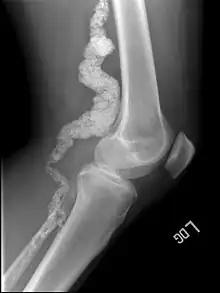

A knee x-ray of a person with ACDC

Arterial calcification due to deficiency of CD73 (ACDC) is a rare genetic disorder that causes calcium buildup in the arteries and joints of the hands and feet, and other areas below the waist.[1] Although patients exhibiting these symptoms have been identified as early as 1914, this disorder had not been studied extensively until recently. The identification of the specific ACDC gene and mutations occurred in 2011. ACDC is caused by a mutation in the NT5E gene, which prevents calcium-removing agents from functioning,.[1][2] Patients with this mutation experience chronic pain, difficulty moving, and increased risk of cardiovascular problems.[1][2] In experiments at the molecular level, treatment with adenosine or a phosphatase inhibitor reversed and prevented calcification, suggesting they could be used as possible treatment methods.[1] There is currently no cure for ACDC, and patients have limited treatment options which focus primarily on removal of blood calcium and improving mobility.[1][2]